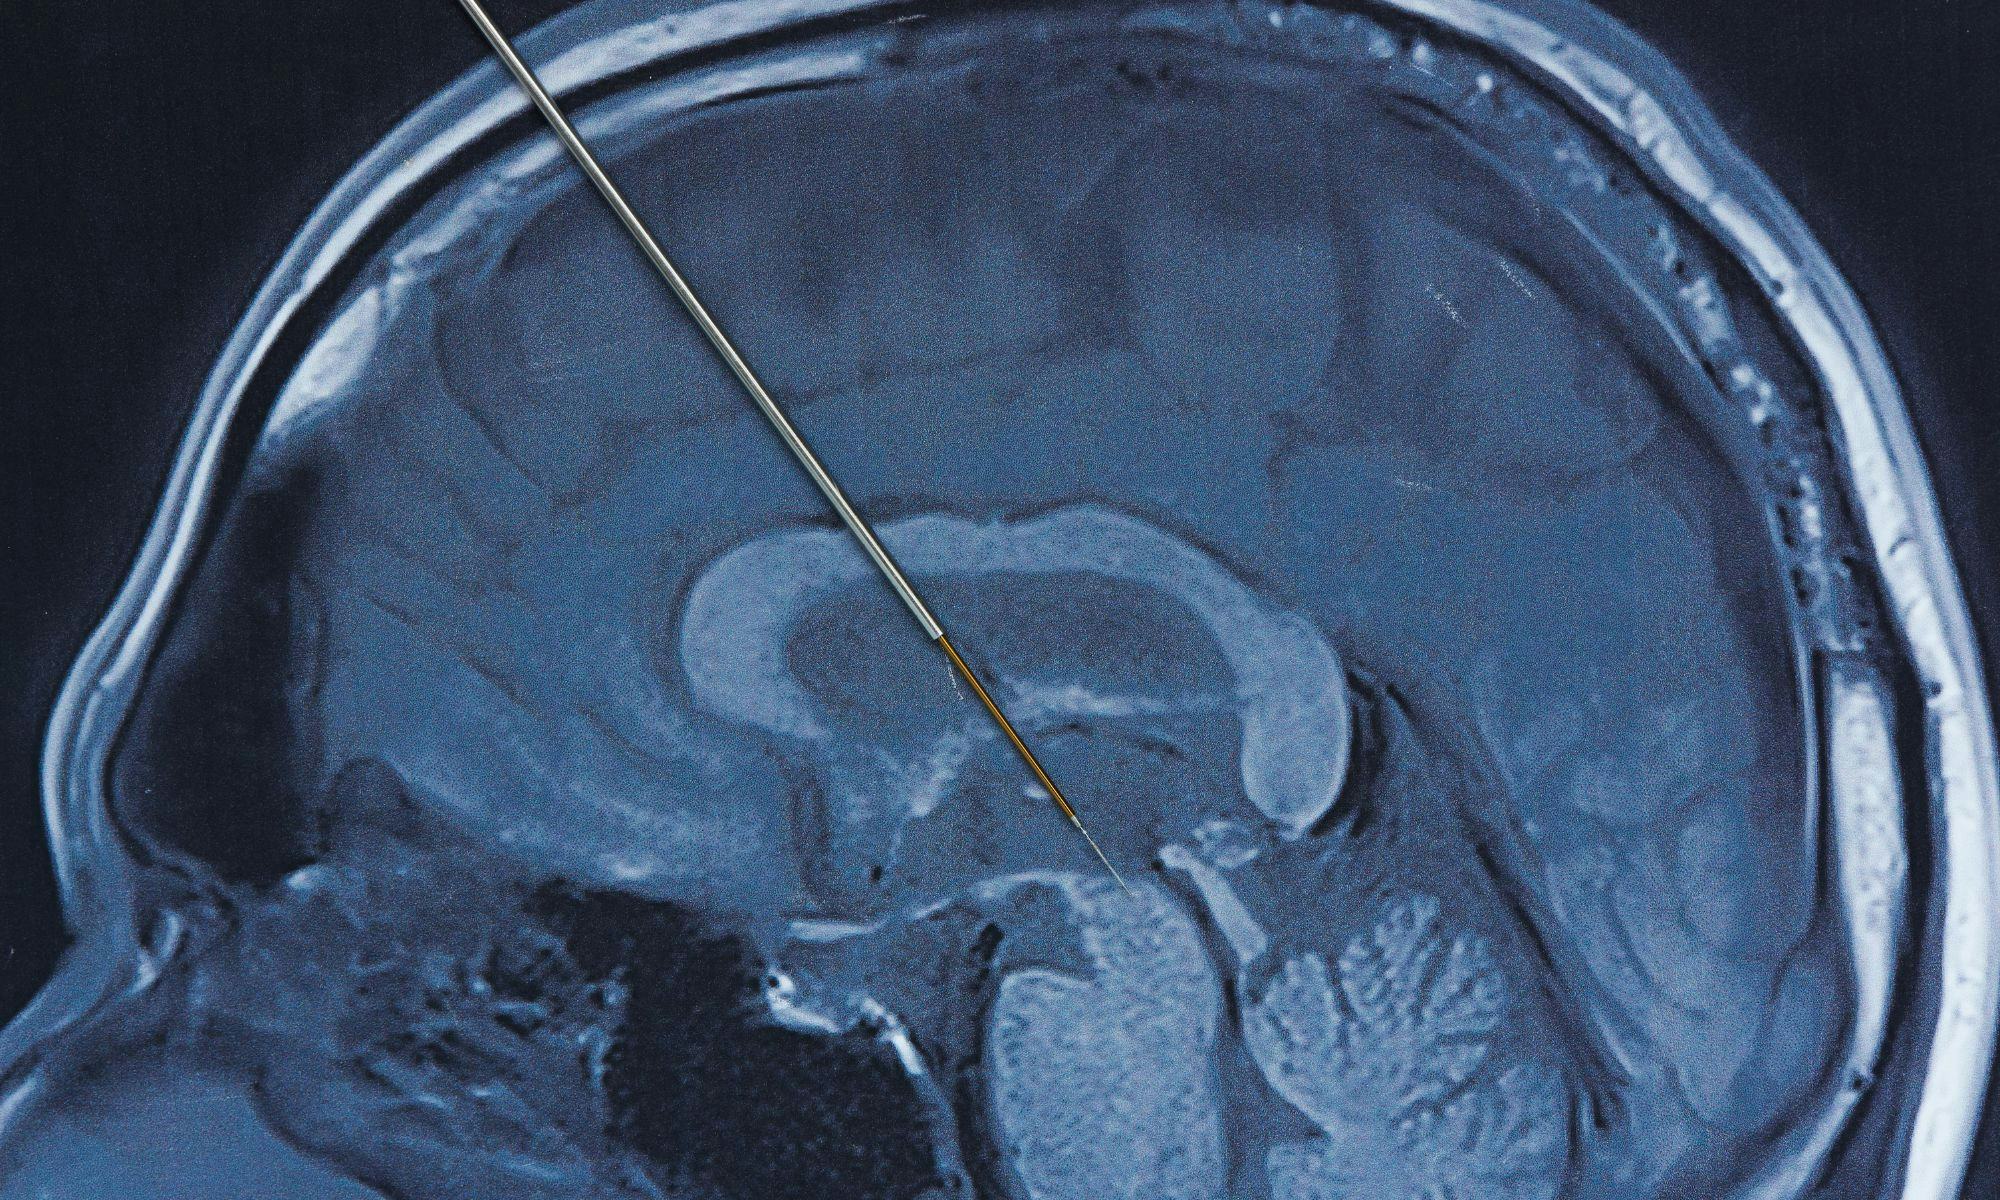

Und dann habe ich 2022 eine zurzeit noch eher unbekannte Hilfe für Zwangserkrankte in Anspruch genommen – und zwar hatte ich das große Glück, eine tiefe Hirnstimulation (THS) durchführen zu lassen bzw. zu erhalten.

Dabei werden zwei Elektroden ins Belohnungszentrum des Gehirns (Nucleus accumbens) eingepflanzt und mittels eines nicht sichtbaren und subkutan verlaufenden Kabels mit einem Schrittmacher verbunden, der sich oberhalb meiner linken Brust unter der Haut befindet. Mittels permanenten, leichten Stromimpulsen “versorgt” dieser Schrittmacher diesen Teil des Gehirns und schafft auf diese Weise über Monate hinweg neue neurologische Bahnen.

Ich kann nicht sicher sagen, woher genau die Besserung kam. Ob sie von dem Schrittmacher oder von den Medikamenten gekommen ist oder ob es sich um eine Kombination aus beidem gehandelt hat, können weder ich noch mein Psychiater genau beantworten. Was wichtig ist: Mir geht es sehr, sehr viel besser - and that’s it. Nichts zählt mehr als das. Die tiefe Hirnstimulation war übrigens ursprünglich für Parkinsonerkrankte indiziert. Im Laufe der letzten ca. 15-20 Jahre wird sie auch für psychiatrische Erkrankungen angewendet.

Obwohl es für die tiefe Hirnstimulation wissenschaftliche Nachweise gibt, ist die Empfehlung der S3-Behandlungsleitlinie dazu sehr konservativ: “Die beidseitige tiefe Hirnstimulation kann unter kritischer Nutzen-/Risikoabwägung bei schwerstbetroffenen Patienten mit Zwangsstörung mit fehlendem Ansprechen auf mehrere leitliniengerechte Therapien durchgeführt werden.“ Es wird also klar empfohlen, eine leitliniengerechte Psychotherapie sowie medikamentöse Standardverfahren durchzuführen, bevor eine tiefe Hirnstimulation in Betracht gezogen werden sollte.